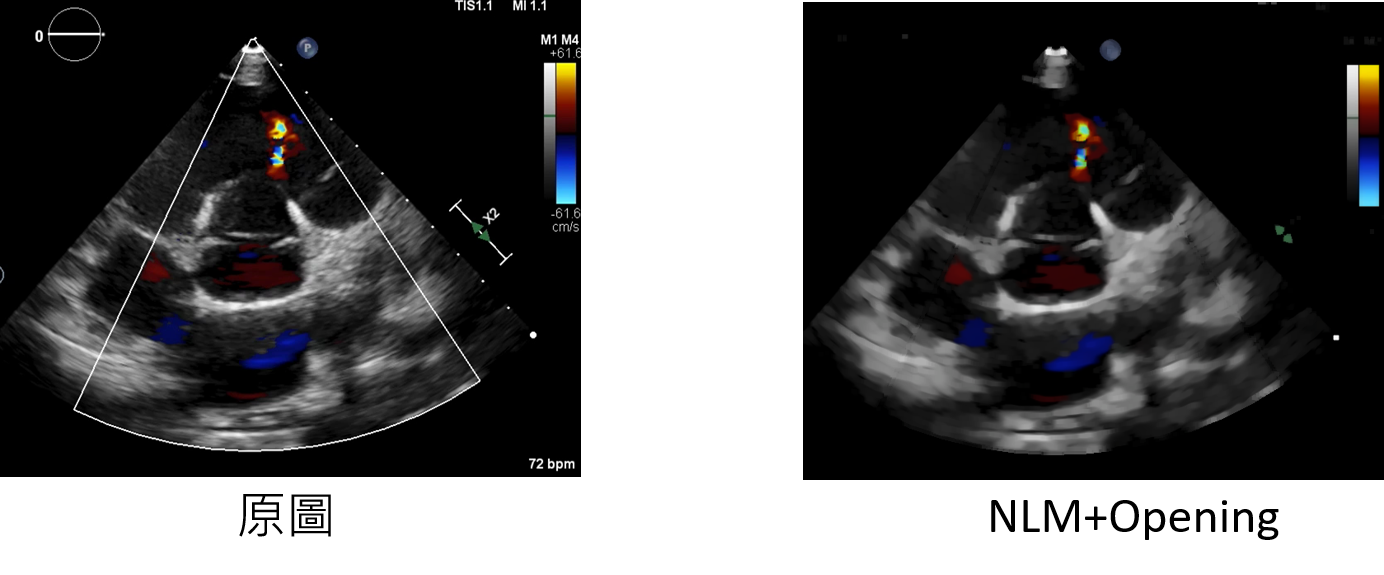

參數說明

NLMOpening:增強方法

h:決定濾波器強度。較高的值可以更好的消除噪聲,但也會刪除圖像細節

templateWindowSize:奇數(推薦值為7)

searchWindowSize:奇數(推薦值為21)

kernel:設定內核的大小

輸入範例:

datagen=CustomDataGenerator(fun="NLMOpening",h=10,templateWindowSize=7,searchWindowSize=21,kernel=5,dtype=int)